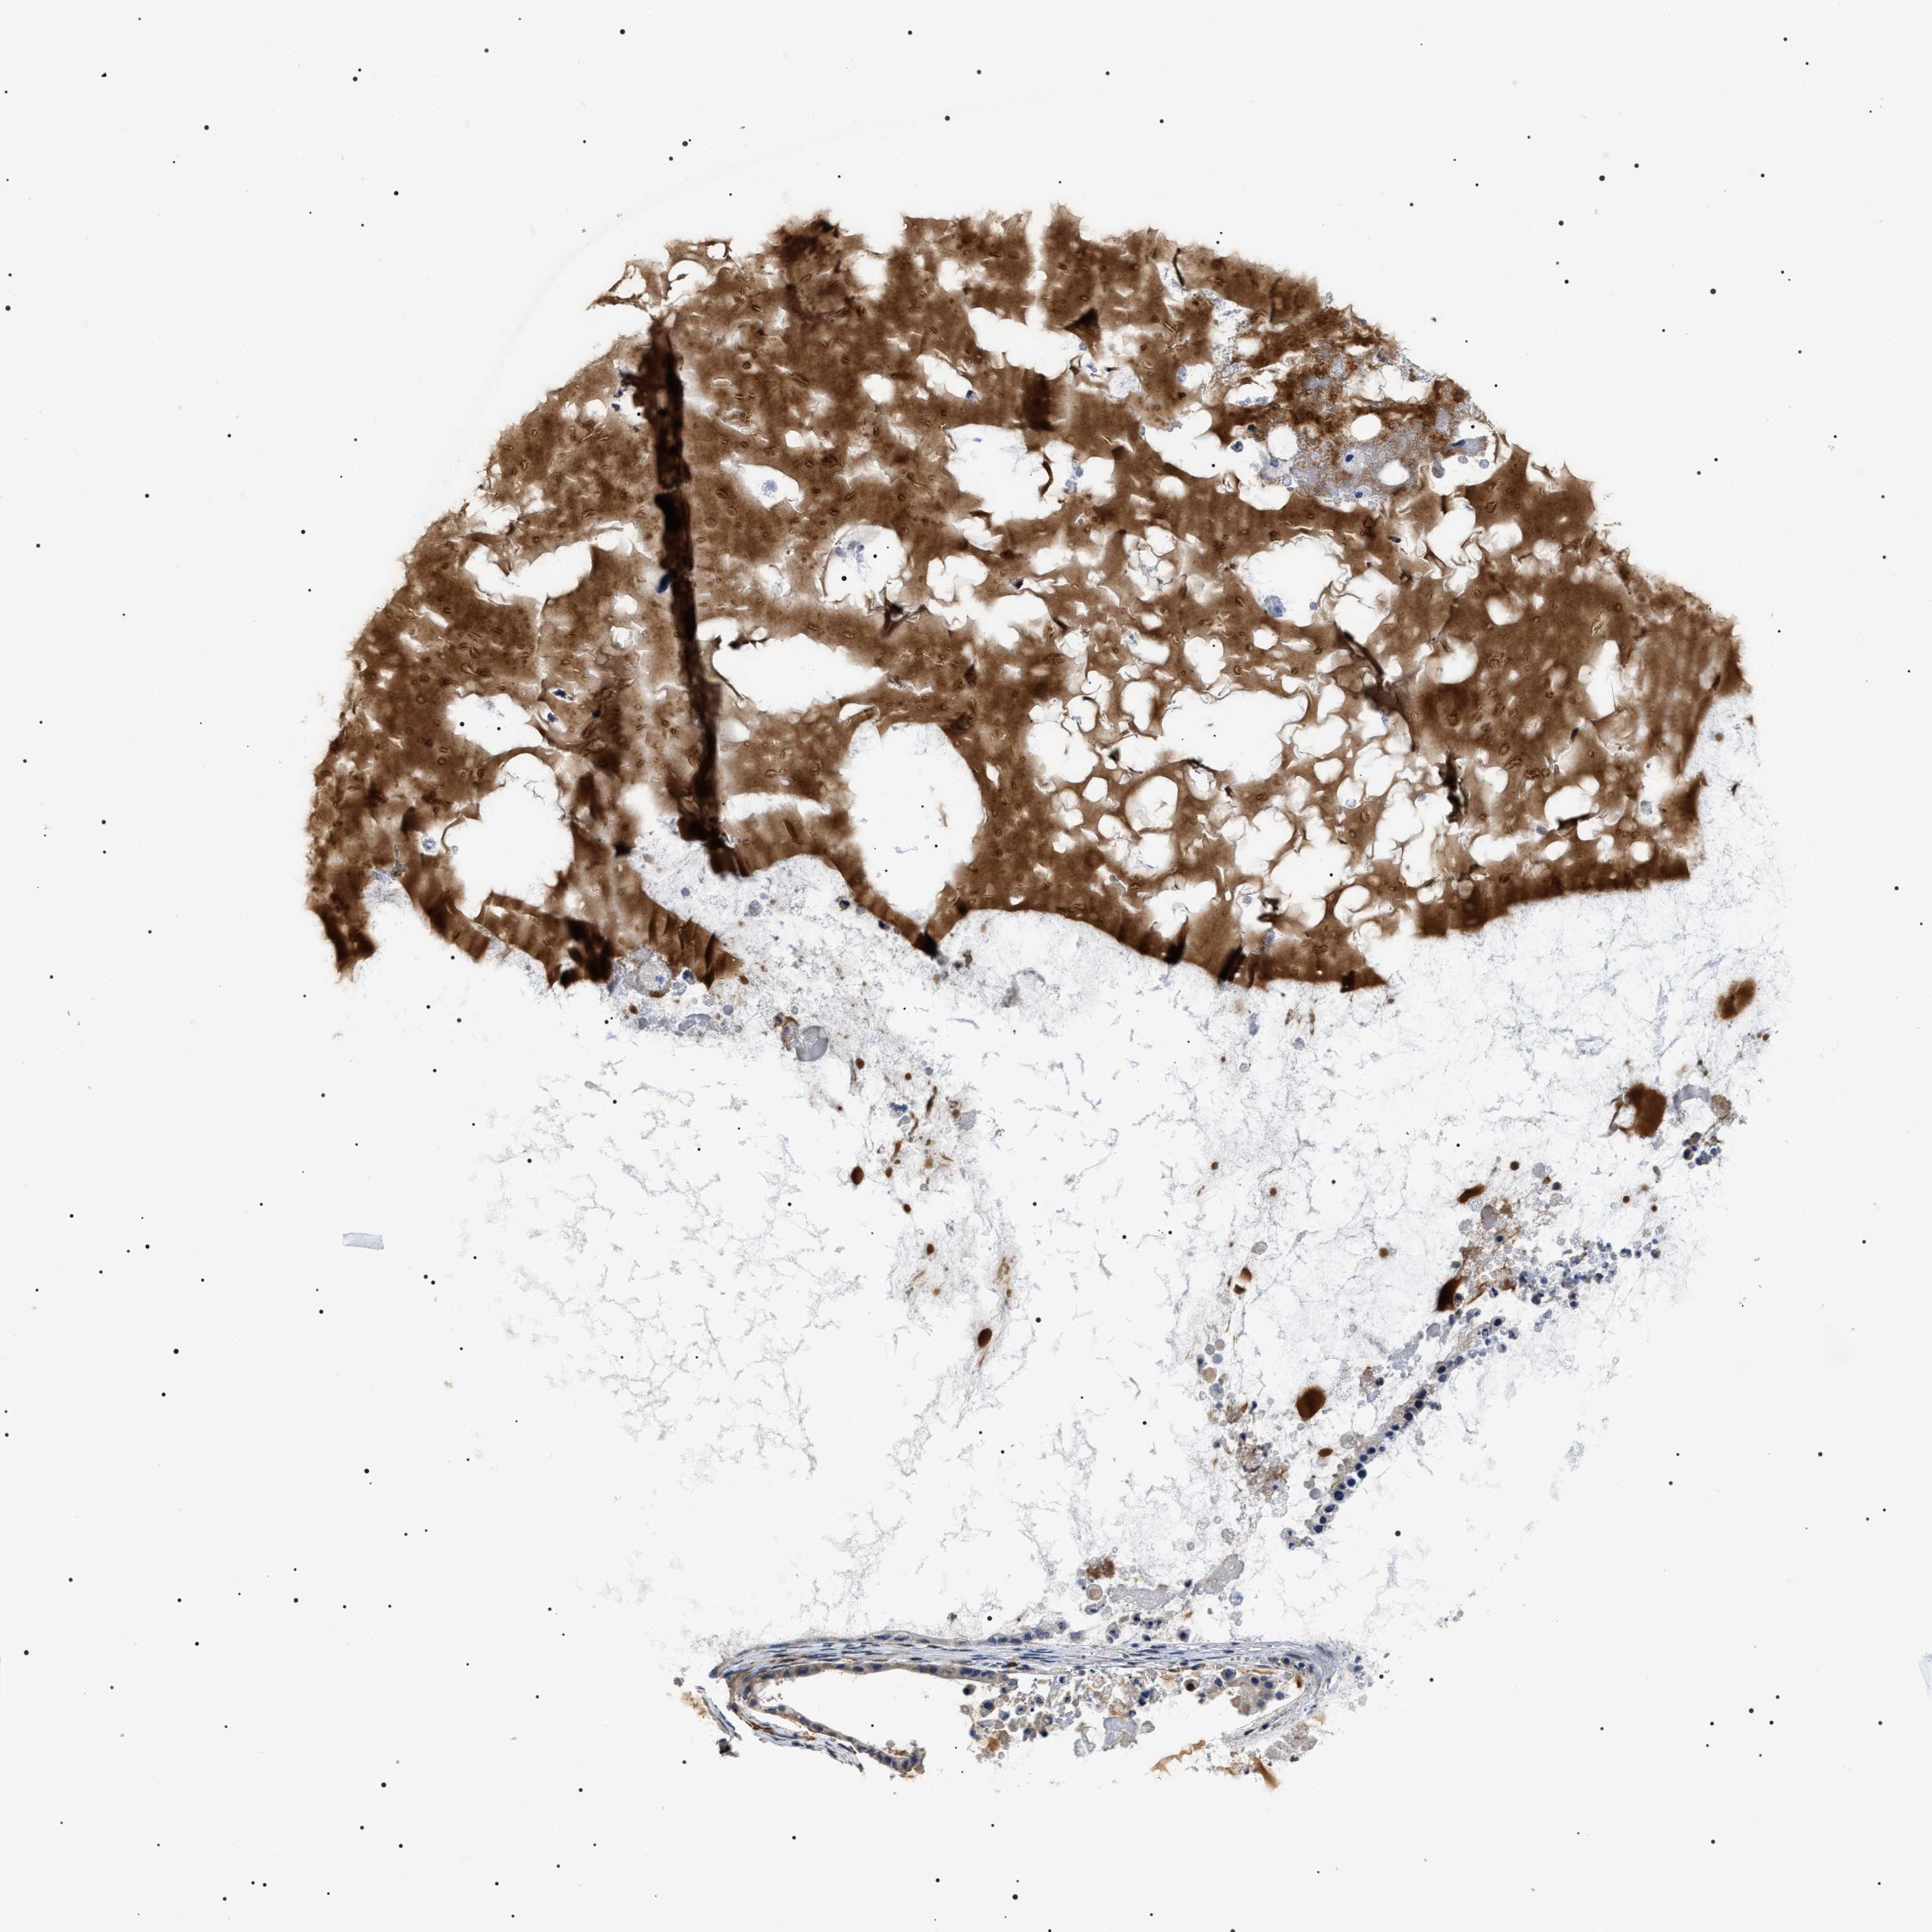

OVARIAN CANCER - Protein expressioni

A mouse-over function shows sample information and annotation data. Click on an image to view it in a full screen mode. Samples can be filtered based on level of antibody staining by selecting one or several of the following categories: high, medium, low and not detected. The assay and annotation is described here.

Note that samples used for immunohistochemistry by the Human Protein Atlas do not correspond to samples in the TCGA dataset.

Antibody stainingi

Antibody staining in the annotated cell types in the current human tissue is reported as not detected, low, medium, or high, based on conventional immunohistochemistry profiling in selected tissues. This score is based on the combination of the staining intensity and fraction of stained cells.

Each image is clickable and will lead to virtual microscopy that enables deeper exploration of all samples and also displays staining intensity scores, fraction scores and subcellular localization as well as patient and tissue information for each sample.

Antibody HPA020386

Staining

High

Medium

Low

Not detected

Intensity

Strong

Moderate

Weak

Negative

Quantity

>75%

75%-25%

<25%

None

Location

Nuclear

Cytoplasmic/membranous

Cytoplasmic/membranous,nuclear

Cystadenocarcinoma, serous, NOS

Carcinoma, endometroid

Cystadenocarcinoma, mucinous, NOS

Carcinoma, NOS